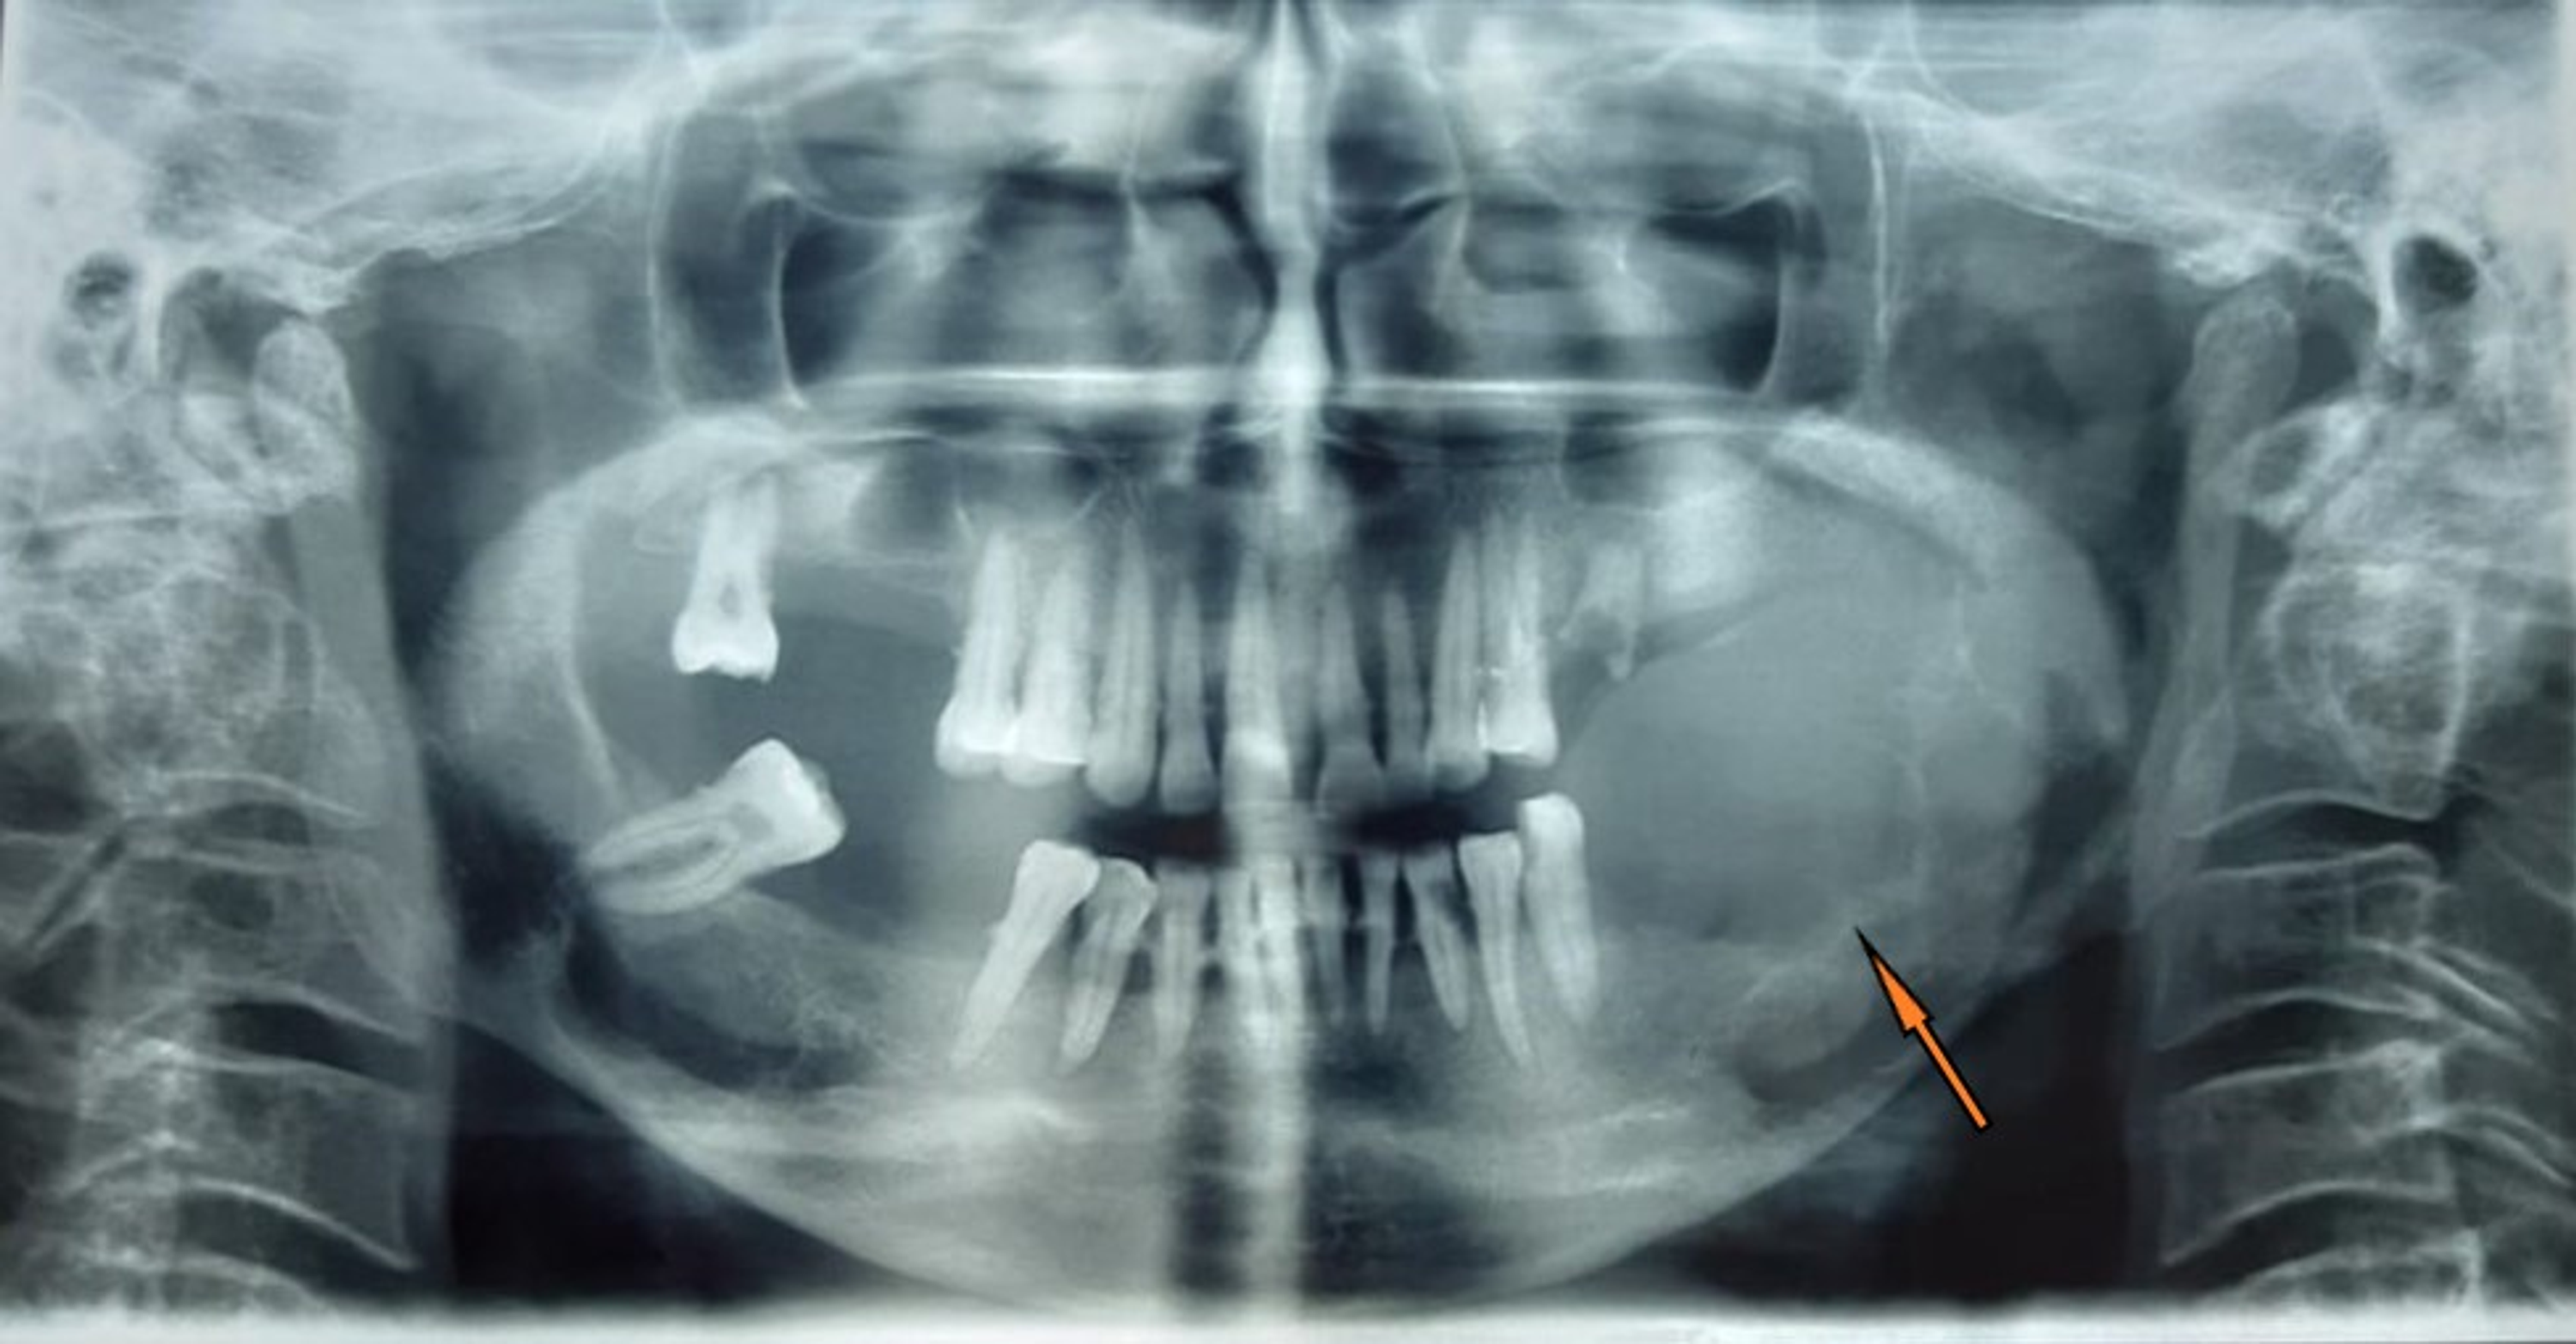

Giant Cell Tumor Mandible . The lesion is common in. in this study, we describe and illustrate a case of gct in the mandible and compare the ihc expression of p63 in. giant cell tumor (gct) of bone is a distinctive neoplasm characterized by abundance of multinucleated giant cells. a histological comparison of the giant cells in the central giant cell granuloma of the jaws and the giant cell tumor of bone giant cell tumors (gcts) are benign bone tumors arising from bone. giant cell tumour (gct) is a rare benign, osteolytic, pseudocystic solitary localized lesion. the appearance is generally distinctive with multinucleated giant cells spread.

the appearance is generally distinctive with multinucleated giant cells spread. The lesion is common in. a histological comparison of the giant cells in the central giant cell granuloma of the jaws and the giant cell tumor of bone giant cell tumour (gct) is a rare benign, osteolytic, pseudocystic solitary localized lesion. in this study, we describe and illustrate a case of gct in the mandible and compare the ihc expression of p63 in. giant cell tumors (gcts) are benign bone tumors arising from bone. giant cell tumor (gct) of bone is a distinctive neoplasm characterized by abundance of multinucleated giant cells.